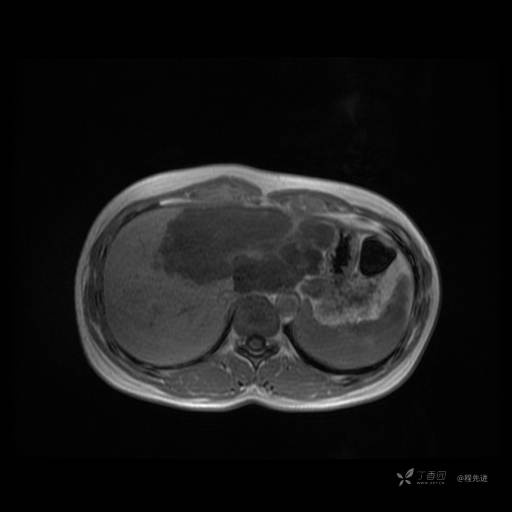

MR平扫+增强

每个序列一张图像(图像太多了,恕不一一发上来)